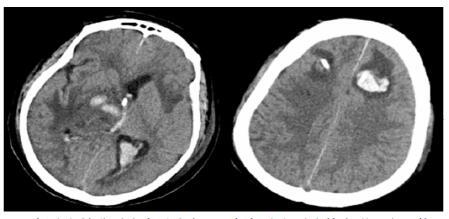

| A:两肺间质性肺炎,下叶为著(2019-06-23);B:(2019-09-30)两肺间质性肺炎,下叶为著,较前(2019-06-23)部分好转 图 3 患者胸部HRCT结果 |

转入ICU后呼吸机辅助通气、甘露醇100 mL/8 h静滴脱水、头孢呋辛1.5 g/12 h静滴抗感染,肠内营养等支持治疗。当晚血常规:白细胞13.3×109/L,中性粒细胞百分比85.3%,C反应蛋白17.1 mg/L,降钙素原0.64 ng/mL。脑室外引流术后次日血化验:白细胞16.6×109/L,中性粒细胞百分比92.8%,C反应蛋白78.4 mg/L;从脑室外引流管留取脑脊液检验:有核细胞6×106/L,红细胞1 960×106/L,蛋白含量1.717 g/L,葡萄糖4.72 mmol/L,细菌培养阴性,涂片未找到细菌;复查头颅CT示:脑室扩张好转,右侧丘脑、左侧岛叶病变伴出血(图 2);胸部CT示,两肺间质性肺炎下叶为著,较前(2019年6月21日)部分好转(图 3)。考虑到炎症指标升高,遂改哌拉西林他唑巴坦3.375 g/12 h静滴抗感染。此后经脑室外引流管反复留取脑脊液送检涂片及培养均阴性。术后第5天行“导航下立体定向颅内病灶活检术+双侧omaya囊置入术”,术中穿刺液呈黄色黏稠脓性,考虑脑脓肿,留取脓液送高通量测序(next-generation sequencing, NGS),并升级为美罗培南2 g/8 h联合利奈唑胺0.6 g/12 h静滴抗感染治疗。术后第7天患者突发血压升高、瞳孔不等大,昏迷程度加深;急查头颅CT示,双侧脑室钻孔引流术后改变,双侧侧脑室引流管走形区出血伴血肿形成;右侧丘脑区积液、积血,双侧脑室积血新发(图 4),甘露醇加量至250 mL/8 h联合地塞米松5 mg/6 h静滴加强脱水;当日术中脓液高通量测序结果回报:皮疽诺卡菌(序列数52 867个)、支气管戈登菌(序列数10个)。确诊脑诺卡菌病,抗菌治疗方案改为亚胺培南西司他丁0.5 g/6 h静滴,联合利奈唑胺0.6 g/12 h和复方磺胺甲恶唑片(0.48 g/片)3片/6 h口服。此后患者仍伴低热,炎症指标呈上升趋势。术后2周患者再次突发血压升高、瞳孔不等大、对光反射消失、神志深昏迷,急查头颅CT示再发脑疝(图 5),急诊行“去骨瓣减压术+脑内血肿清除术”,术后患者仍呈深昏迷状态,双侧瞳孔散大、对光反射消失,次日自动出院。